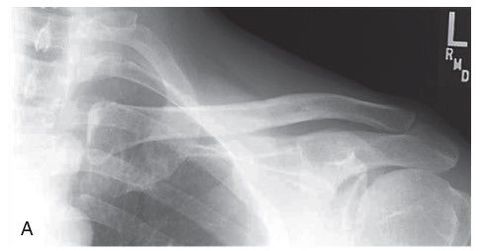

Bilateral AC Joints w/ weights

AP AC and SC Joints weight bearing and non weight bearing 72 SID 65-80 kVp 14x17 IR crosswise CR @ manubrium expose during suspended respiration *take first exposure without weights *8-10lb weights should be attached to wrists so the arms and clavicles will be relaxed for the 2nd projection